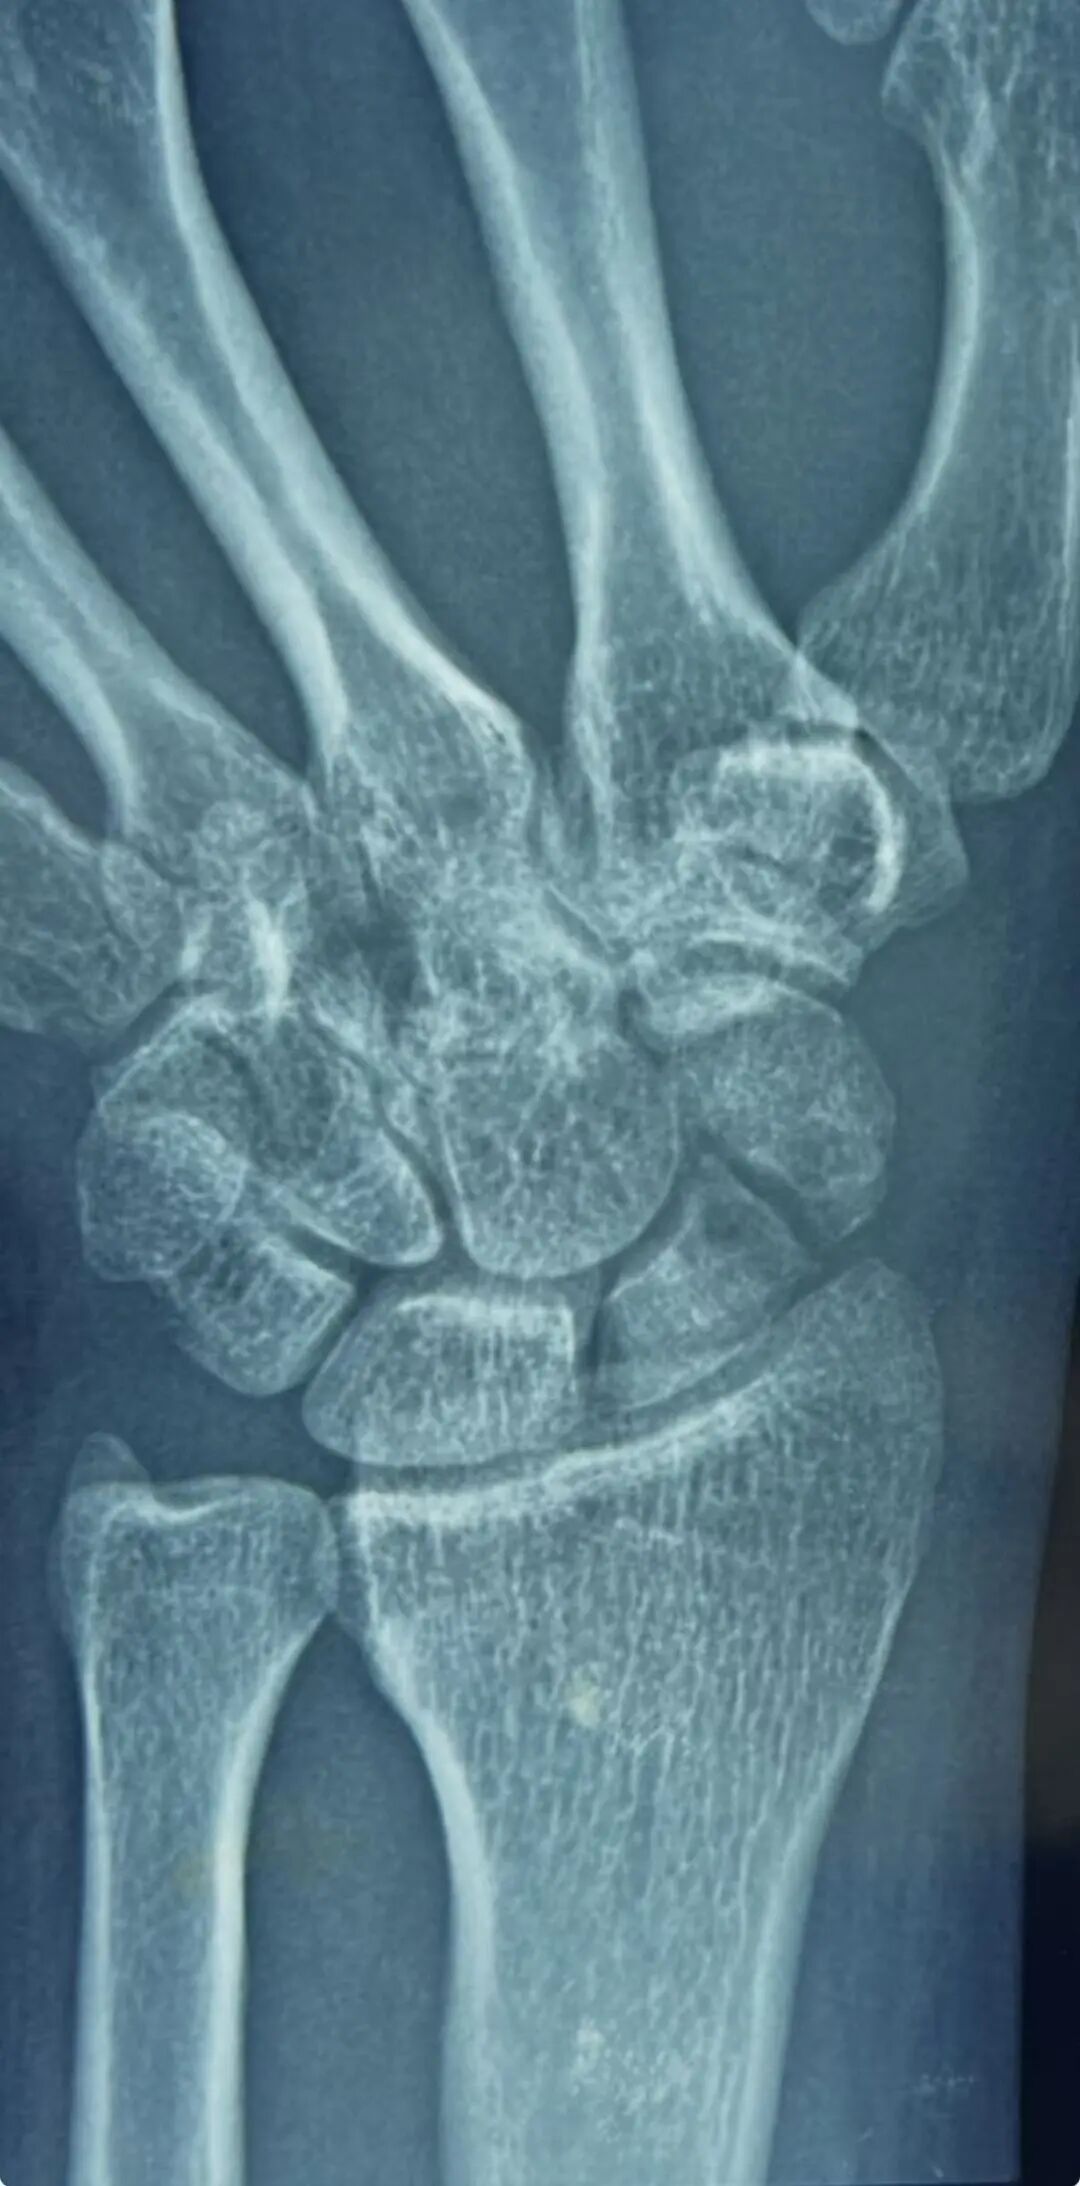

郭阳院长仔细翻阅他 20 多年来的病历,结合最新的检查结果,指着影像片上的病灶,耐心解释:“你这是典型的陈旧性舟骨骨不连,骨折端已经硬化、萎缩,周围腕关节也出现了代偿性磨损,普通手术很难彻底清理硬化骨、稳定固定,容易再次不连,需要植骨重建 + 内固定技术,才能从根源上解决疼痛,恢复腕关节功能。”

手术过程中,发现骨折断端磨损的非常厉害,已经形成了假关节,凭借积水潭手外科精湛的显微操作技术,郭阳院长精准定位骨折部位,细致清理硬化骨组织,取自体尺骨鹰嘴骨植入骨缺损区,再用螺钉牢固固定,一步步为陈先生重建了健康的腕关节结构。

术后复查的 X 线片上,曾经断裂、硬化的舟骨被稳稳复位,植骨块位置良好。